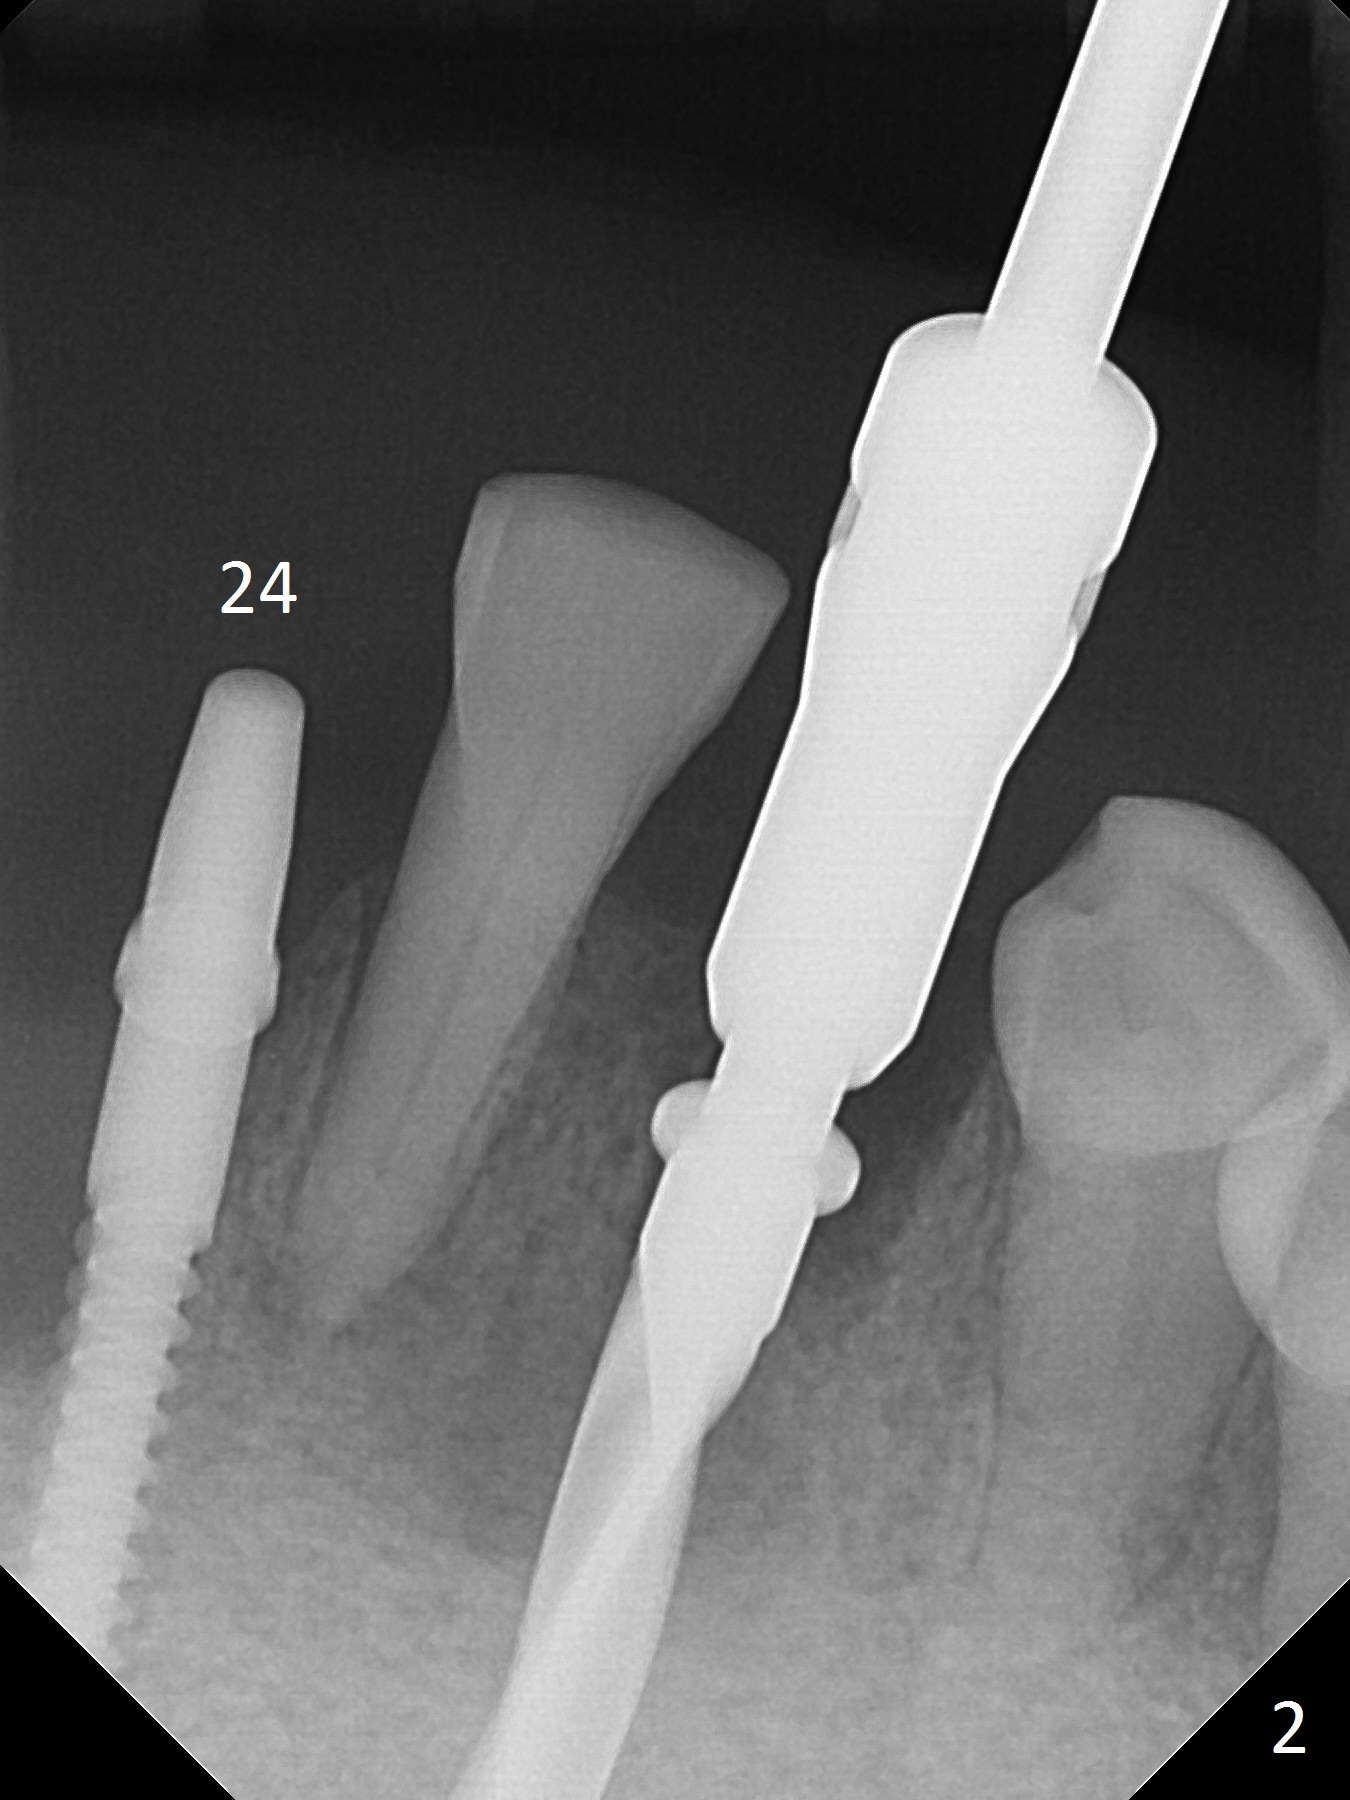

Before surgery, the patient reports that the tooth #25 has inclined to the position of #24 since the latter was extracted (Fig.1). After extraction of the tooth #25, there seems to be more bone vertically at the site of #24 than that of #25. Therefore the osteotomy is initiated at #24. The edentulous space is 9 mm mesiodistally, whereas the incisor width is 6 mm. The first pilot drill is fractured (1.2 mm). The latter is retrieved with incision. With better visibility, the initial osteotomy is found buccal. When a 3x14(2) mm dummy 1-piece implant is being placed partially, the buccal plate seems to be thin. A 2.5x14(4) mm 1-piece implant is placed instead with stability (Fig.2).

The depth of the osteotomy at #22 is 2-3 mm more than the expected implant length (Fig.2 with 2.7 mm drill in place). The implant at #22 (3.8x18 mm with insertion torque more than 50 Ncm) has clearance from the Incisive Canal and Mental Loop (Fig.3 red dashed line). Allograft with Osteogen is placed around the implants (Fig.4 *) in addition to Osteogen plug (cut in a thin layer) placed against the buccal wall of the socket at #22 (potential leakage). After suturing (Fig.5) and provisional cementation (Fig.6), periodontal dressing is applied (Fig.7). The implants seem to be ready for impression 4 months postop (Fig.8).